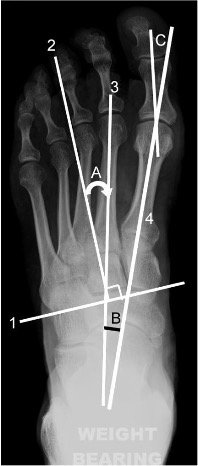

Line 1 = bisection of lesser tarsus

Line 2 = longitudinal axis of lesser tarsus

Line 3 = longitudinal axis of metatarsus

Line 4 = midline axis of first metatarsal

A = metatarsus adduction angle

B = metatarsus primus adductus (or intermetatarsal) angle

C = hallux valgus angle

Longitudinal axis of the metatarsus

A longitudinal bisection of the second metatarsal.

Metatarsus adduction angle

Between the longitudinal axis of the metatarsus and the longitudinal axis of the lesser tarsus.

Normal: <15°

A greater angle indicates metatarsus adductus or deviation of the forefoot to the midline. Severe metatarsus adductus may be associated with hindfoot valgus (e.g. skew foot).

Hallux valgus angle

Between the longitudinal bisection of the first proximal phalanx and first metatarsal.

Mild: 16-25°

Moderate: 26-35°

Severe: >35°